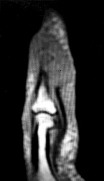

Explanation

Recent high-quality level I evidence (such as the Willits study) has demonstrated that when an early functional rehabilitation protocol (early weight-bearing in a functional brace) is utilized, the re-rupture rate of non-operative management is equivalent to that of operative repair, while completely avoiding surgical risks such as wound breakdown and sural nerve injury.